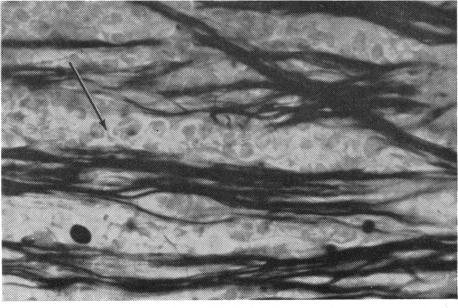

RETINAL PATHOLOGY AFTER CENTRAL RETINAL VEIN OCCLUSION.

Br J Ophthalmol. 1961 Oct;45(10):683-94. doi: 10.1136/bjo.45.10.683.